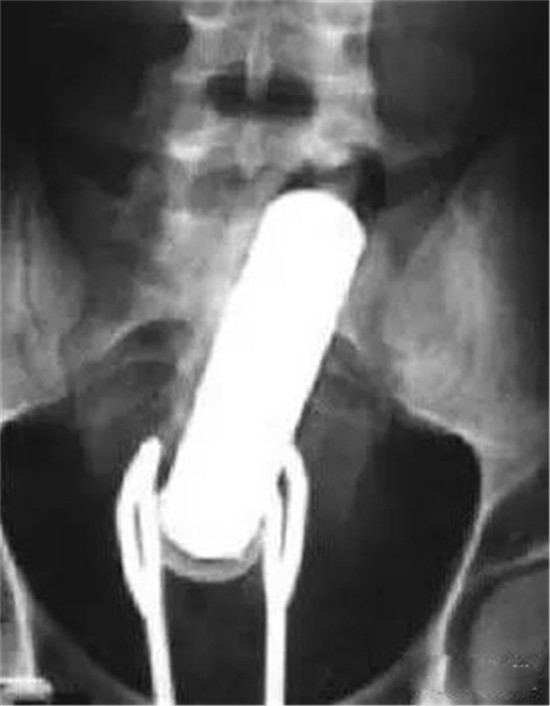

这是一个啤酒瓶。男性。

上面是一个啤酒瓶在大肠里。病人是男性。这是常见的肛门内异物。

这种情况,往往只要给病人打上全身麻醉,肛门松弛后,就可以用卵圆钳经过肛门把啤酒瓶拉出来。